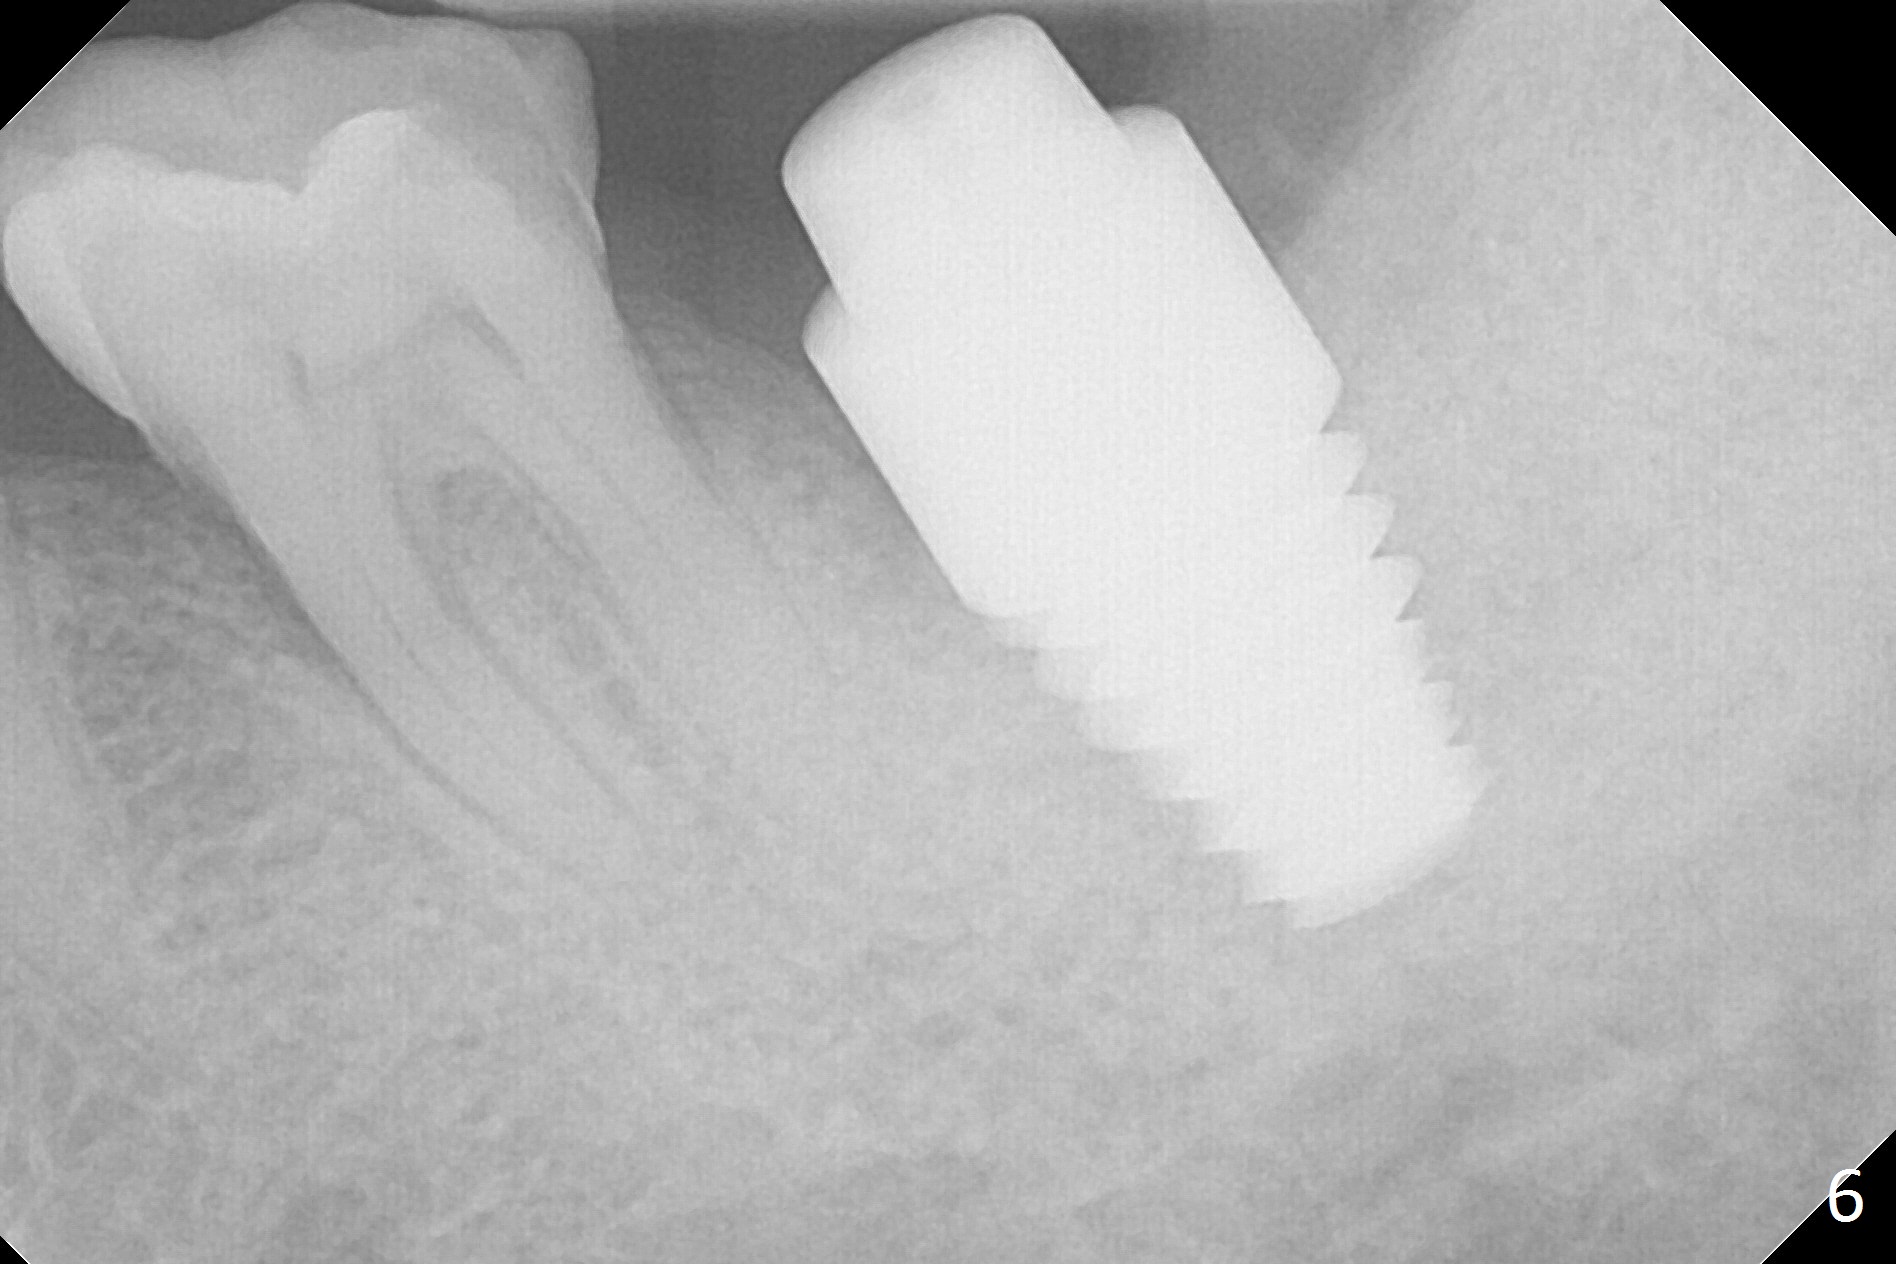

When the tooth #18 is extracted, the buccal and lingual plate are absent. Initial osteotomy is established in the middle of the socket (Fig.1). After 4.3 mm Magic Drill (15 mm from the buccal gingival margin, new bone ~ 4 mm), a 5x9 mm IBS dummy implant is placed with correct trajectory (Fig.2). Since the bone density is seemingly high, the same size of a definitive implant is placed with primary stability. The trajectory is found not ideal after bone graft and insertion of an abutment (data not shown). The stability is lost when the trajectory is changed. No primary stability is achieved with a larger (5.5x9 mm) implant. Tatum tapered taps (6x17, 7x17 and 8x17 mm) are used. The latter obtains stability with contact with the mesial and distal crests (Fig.3 *). A 8x14 mm tissue-level implant is placed with insertion torque ~ 55 Ncm (Fig.4). A 6x3 mm abutment (Fig.4 A) is placed to retain an immediate provisional (Fig.5 P). The drawback of the extra large implant is lack of bone buccolingually. Oral hygiene is emphasized so that the buccal and lingual bone have chance to regenerate. Fortunately there appears to be no paresthesia postop.

It appears that the patient chews on the left postop, since the provisional perforates with loose abutment nearly 3 months postop and the tooth #3 has occlusal sensitive chip. The implants seems to have osteointegrated (Fig.6). To improve oral hygiene, the provisional is not recemented. The patient will return for impression in 2 weeks. It appears that there is short healing time for large implant. There is no bone loss 7 months post cementation (Fig.7). The buccal gingiva is lightly erythematous without tenderness 1 year 7.5 months post cementaion. Water pik is being used, although chronic periodontitis is not under control. Retrospectively, surgery should be shifted to socket preservation when a moderate implant (5 or 5.5 mm) fails to achieve primary stability. The extra large implant (8 mm for example) leaves a little gap buccolingually. Guided surgery would allow precise placement of the moderate implant without change in trajectory. The crown becomes loose because of occlusal perforation and limited vertical space. When a new crown is cemented, the bone density around the coronal threads is high (Fig.8 *). While the bone remains stable at #4 (6 months post RCT), 13 (4 years 6 months post cementation) and 18 (2 years 5 months post cementation), there is severe bone loss at #2 and 31 (Fig.9).